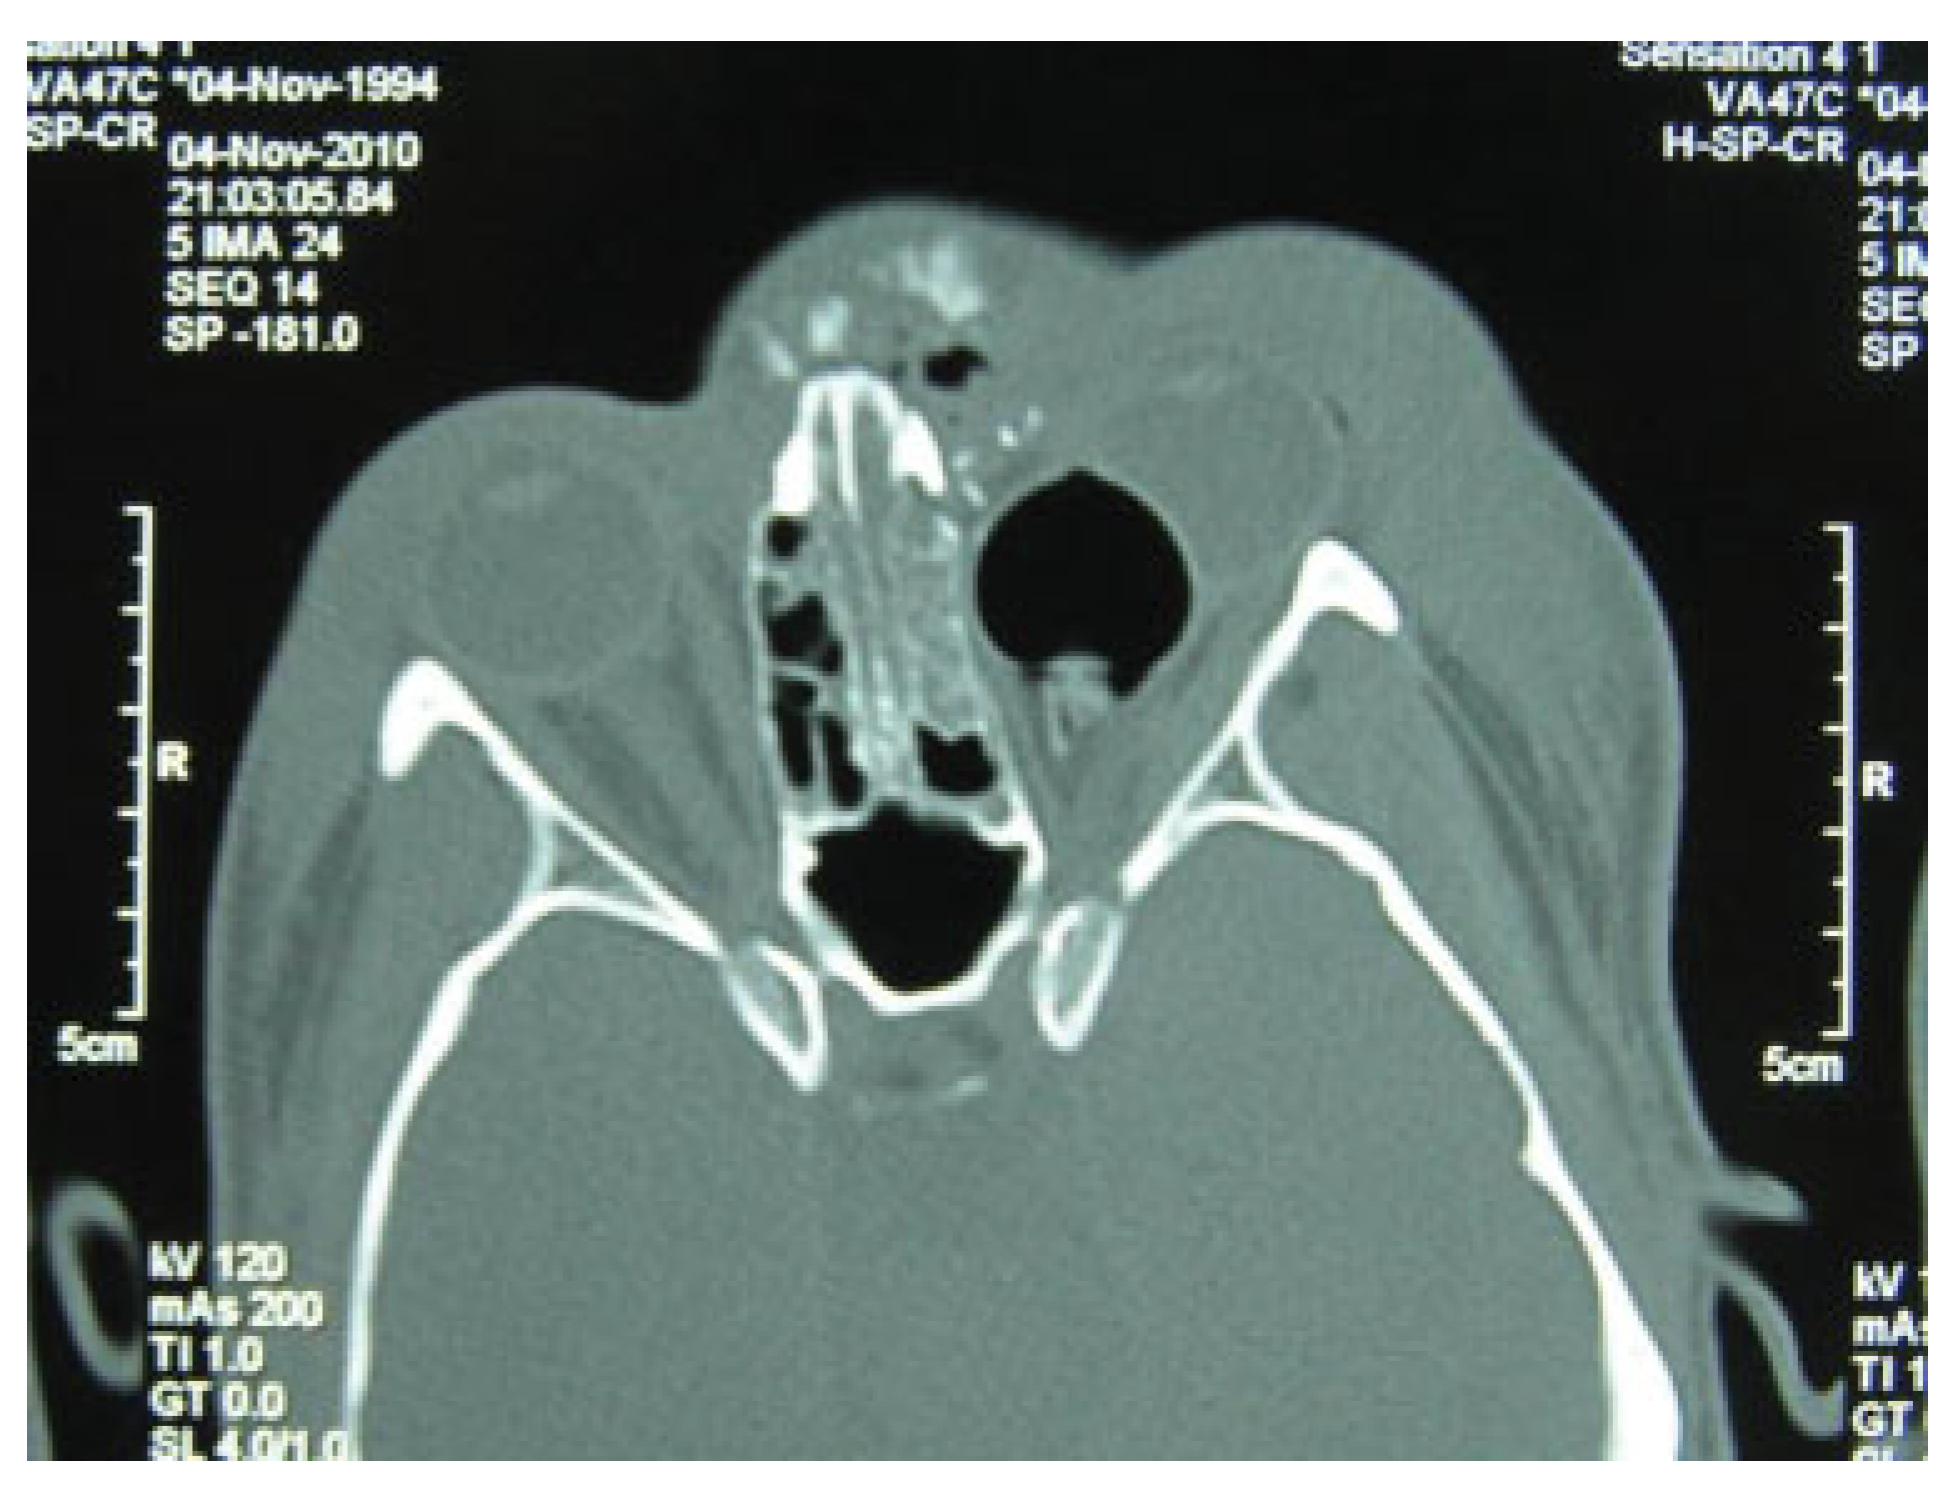

Iatrogenic Oculocardiac Reflex in a Patient with Head Injury

:Case Report